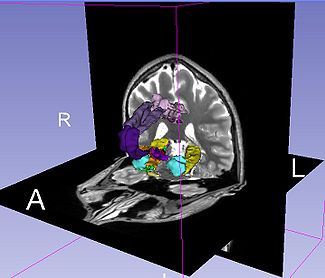

The Query Results panel shows the result of a query, consisting of all the associated predicates and parts for the query. The Figure User Page GUI shows the result of a simple query "limbic system".Additionally, the interface also shows a Comment that contains any relevant textual information about the query obtained from the ontology. The user can refine a search by selecting from the query result. Optionally, the user can also select by clicking on any selection from the Query History or Favorite Queries panel to redo search and visualization. The interface supports the multiple selections to form complex queries. The visualization resulting by searching with the query "Limbic system" is shown below.

Simple query is a self-contained individual string that is matched in entirely with the ontology. An example of a simple query is "limbic system". The result of this query is shown above.